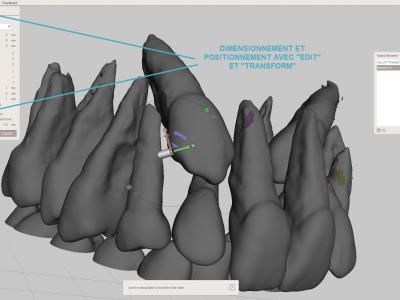

- Etape de réparation : réparer les "trous" du maillage 3D avec l'outil "Inspector" et "Auto repair all" afin de ne pas avoir d'erreurs d'impression

- Etape de finitions : reboucher des manques, adoucir des pics ou des crêtes avec les différents outils "Sculpt"

- Exporter le fichier STL à imprimer